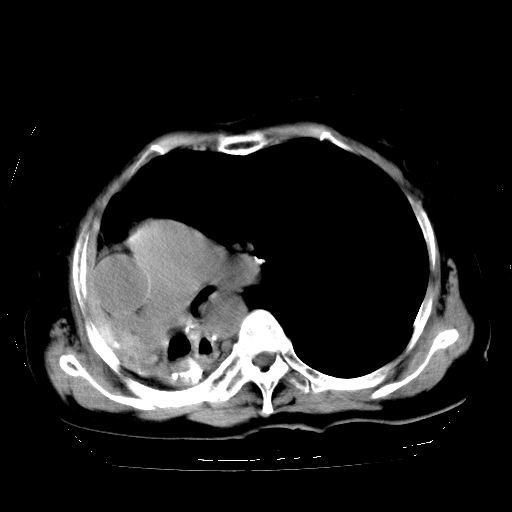

标题: CT23991:女,72岁,咳嗽、憋气一周。 [打印本页]

女,72岁,咳嗽、憋气一周,十年前曾患肺结核及胸膜结核。

右侧毁损肺,右侧纵隔疝,左肺代偿!

1.右侧损毁肺伴胸膜钙化,2.左肺小结节灶,良性可能大,注意复查。3.肝脏左叶囊肿。4.先天性一侧肺不发育待出外(右侧胸廓无明显塌陷)。对比原片应该非常有帮助。

右侧肺毁损,左肺代偿性肺气肿,纵隔疝。